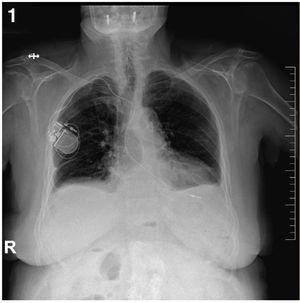

Caso clínicoPaciente mujer de 88 años con clínica de mareos recurrentes, de dos meses de evolución, que consulta a urgencias por episodio sincopal asociado a crisis convulsiva, donde tras la realización de estudios complementarios y nuevo episodio convulsivo presenciado, presenta asistolia por lo que son iniciadas maniobras de resucitación con recuperación posterior y desde el punto de vista electrocardiográfico desarrollando un bloqueo aurículo-ventricular completo transitorio, motivo que deriva su ingreso en cardiología para estudio electrofisiológico más extenso. Es entonces cuando tras la realización del traslado a su centro de referencia precisa la inserción de un marcapasos externo y de la administración de isoprenalina. A su llegada, se deriva a quirófano donde se realiza implante de marcapasos definitivo monocameral (VVI), con posterior mejoría, y traslado a planta de hospitalización convencional (figs. 1 y 2).